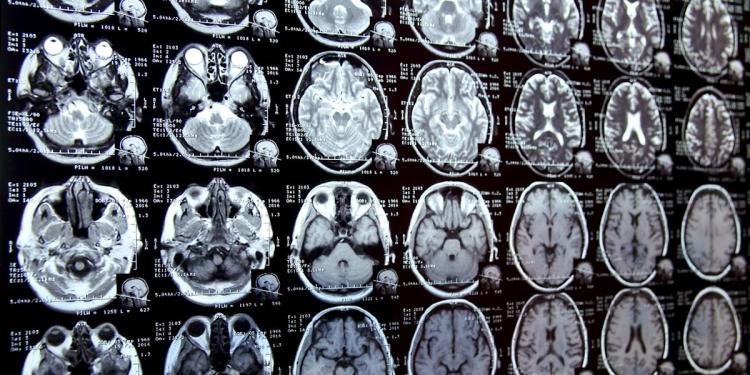

Recent research indicates that the average human brain contains approximately five plastic bottle caps’ worth of microplastics, with levels rising significantly over the past eight years. This accumulation of microplastics is linked to various health issues, including cognitive decline and reproductive concerns, posing serious risks not just to individuals but also to ecosystems and public health. Efforts to combat plastic pollution include bans on single-use plastics in several countries, while researchers continue to explore innovative solutions for reducing microplastic exposure.